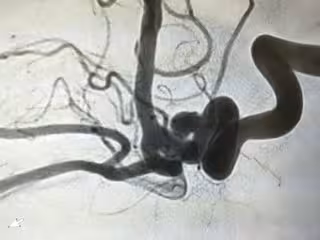

Los aneurismas se forman como protuberancias o globos aerostáticos anormales en una arteria y, si se rompen, pueden provocar graves complicaciones de salud o incluso la muerte. Algunos aneurismas pueden existir durante mucho tiempo sin romperse, y la cirugía implicada en el tratamiento de los aneurismas puede ser bastante arriesgada, por lo que se necesita un parámetro para ayudar a guiar a los cirujanos.

Hoy en día, se toman las decisiones de tratamiento principalmente al evaluar los parámetros geométricos, como el tamaño de un aneurisma, que se obtiene a partir de imágenes médicas. Pero se sabe que la mecánica de fluidos es un factor importante en la iniciación, el crecimiento y la ruptura de los aneurismas.